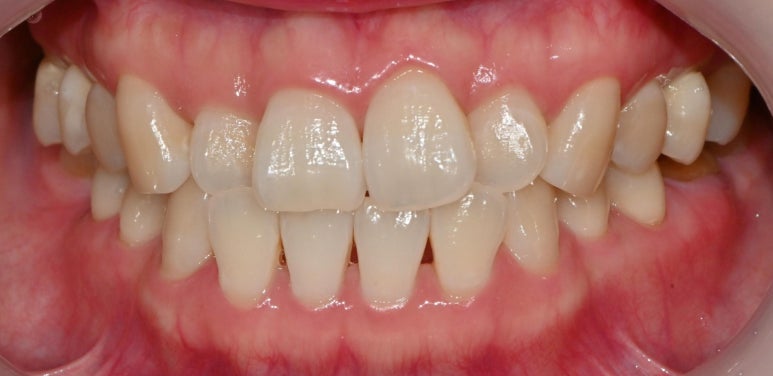

서울대입구역 교정 치과 를

처음 찾아오셨을 당시

구강을 살펴보면

윗니들이 삐뚤빼뚤한 것이 관찰됩니다.

우리는 이것을 총생(crowding)이라

부르며,

두 개의 앞니도 정중선이 맞지 않고

한쪽으로 쏠려있어 보이네요.

또한 사진에서는 잘 보이지 않으나

맨 뒤에는 사랑니도 남아있었습니다.

서울대입구역 교정 치과 에서

모든 진료가 끝나고 난 뒤

구내 모습을 보면

본래의 색과 비슷한 크라운을 올려드렸으며

저작 기능을 잘 수행할 수 있도록

적절한 사이즈의 보철을 제작하여

수복해 드렸습니다.

윗니도 마찬가지로

총생을 개선함과 동시에

본래의 자리로 돌아가지 않도록

안쪽에 유지 장치를 부착해두었습니다.